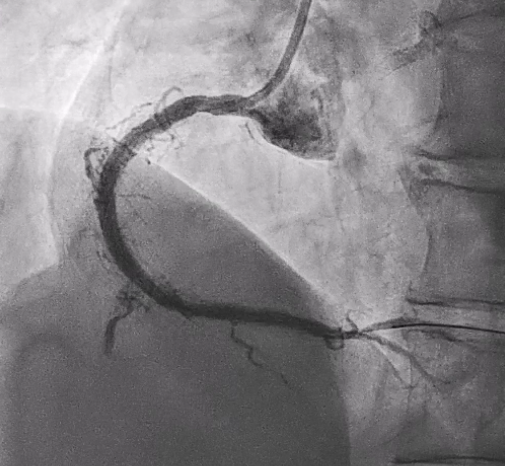

In this coronary catheterization procedure, a guidewire was used to cross the lesion and advanced to the posterolateral branch (PL). An intravascular ultrasound (IVUS) examination was conducted, revealing a pseudoaneurysm in the mid-right coronary artery (m-RCA). To cover the pseudoaneurysm, a 3.5 x 16 mm cover stent was deployed in the m-RCA at a pressure of 16-18 atmospheres for 15-20 seconds, repeated twice. Subsequently, the cover stent was further post-dilated with a 3.75 x 15 mm non-compliance balloon at 18-20 atmospheres for 10 seconds, also performed twice. Optical coherence tomography (OCT) was then performed, showing a post-dilation stent MSA of 7.40 mm² with good apposition and expansion. The cover stent was additionally dilated with a 4.0 x 30 mm drug-eluting balloon (DEB) at 6 atmospheres for 60 seconds. The final angiography demonstrated TIMI grade 3 flow without any extravasation.

Case Summary

Post-intervention angiography demonstrated improved blood flow in the affected artery. The RCA pseudoaneurysm was effectively sealed, and subsequent imaging confirmed appropriate stent placement. The use of IVUS and OCT allowed for optimal sizing and placement, leading to a successful outcome.

This case demonstrates that cover stents are a valuable tool in treating coronary pseudoaneurysms, with advanced imaging techniques improving procedural outcomes. Optimal stent deployment is critical in minimizing complications and ensuring long-term vessel patency.